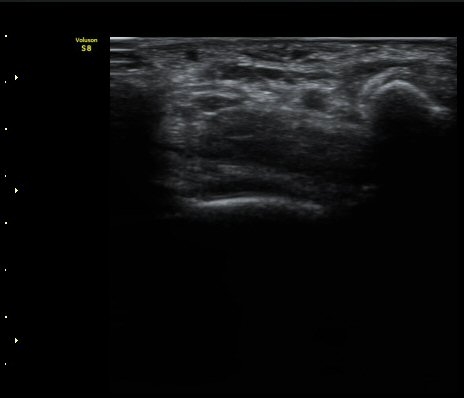

ÃÊÀ½ÆÄ °Ë»ç

¤º